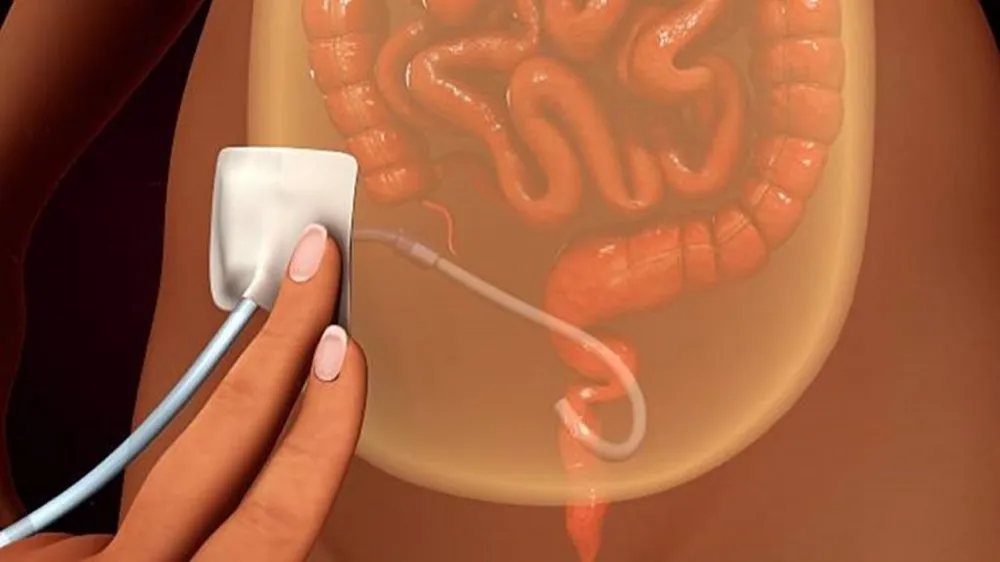

Disfunção do cateter de diálise peritoneal

Disfunção do cateter de diálise peritonealConfere aqui um fluxograma para conduzir disfunção do cateter de diálise peritoneal

Valkercyo Feitosa

3 anos atrás

Profilaxia com antifúngicos em pacientes em diálise peritoneal

Profilaxia com antifúngicos em pacientes em diálise peritonealConfere essa dica prática essencial no manejo das peritonites

Valkercyo Feitosa

3 anos atrás